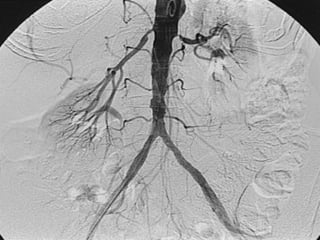

Noninvasive Hemodynamic Assessment  segmental pressure technique Exercise (treadmill) testing Limb plethysmography Doppler and Duplex Ultrasonography Computed tomography  angiography  (CTA) Magnetic resonance angiography (MRA) Digital subtraction angiography (DSA) Diagnosis